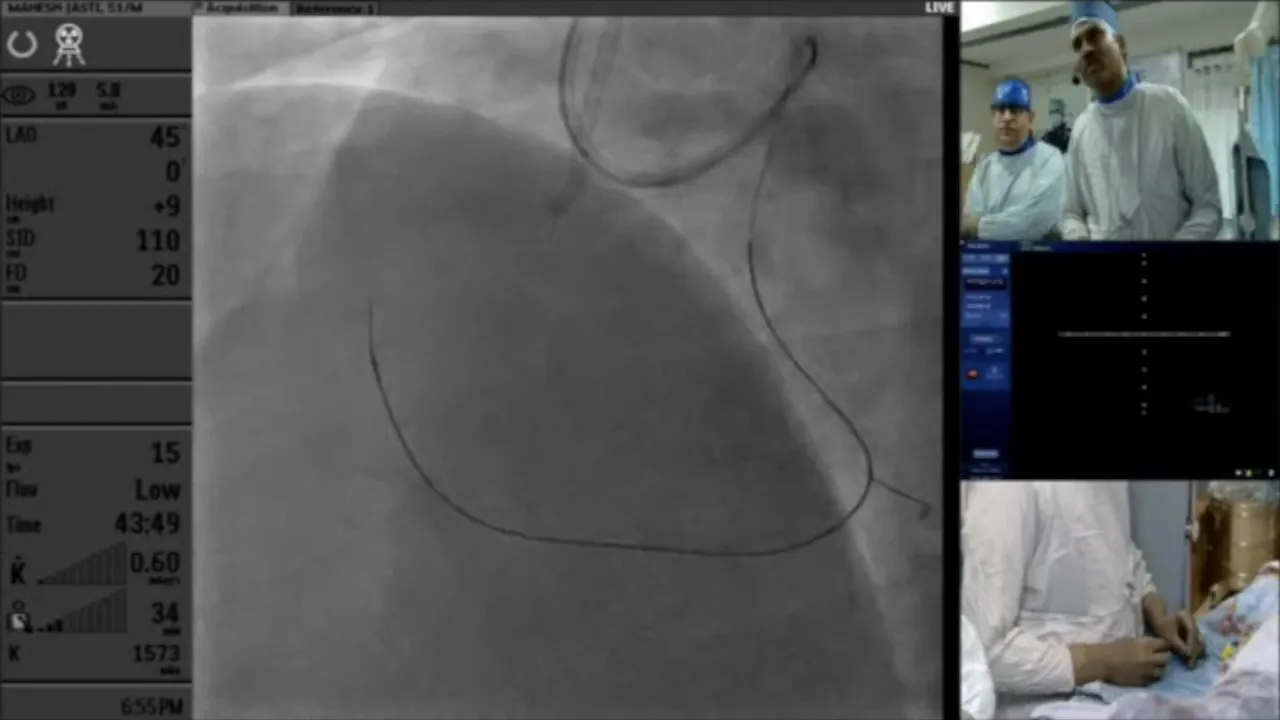

In this detailed live case presentation, Dr. Sharath Reddy walks us through a challenging coronary intervention involving a simple RCA CTO that evolved into an antegrade nonstarter. Join us as we explore the intricacies of catheter selection, wire navigation, and the decision-making process in real-time.

This case revolves around a complex coronary intervention involving a challenging RCA CTO. Initially straightforward, the situation quickly escalated into an antegrade nonstarter. Our goal is to dissect the decision-making process, focusing on catheter selection and wire navigation.

As we dive into this case, it’s crucial to grasp the anatomy and the specific challenges posed by the patient’s coronary vasculature. This understanding sets the stage for the strategic decisions made throughout the intervention.